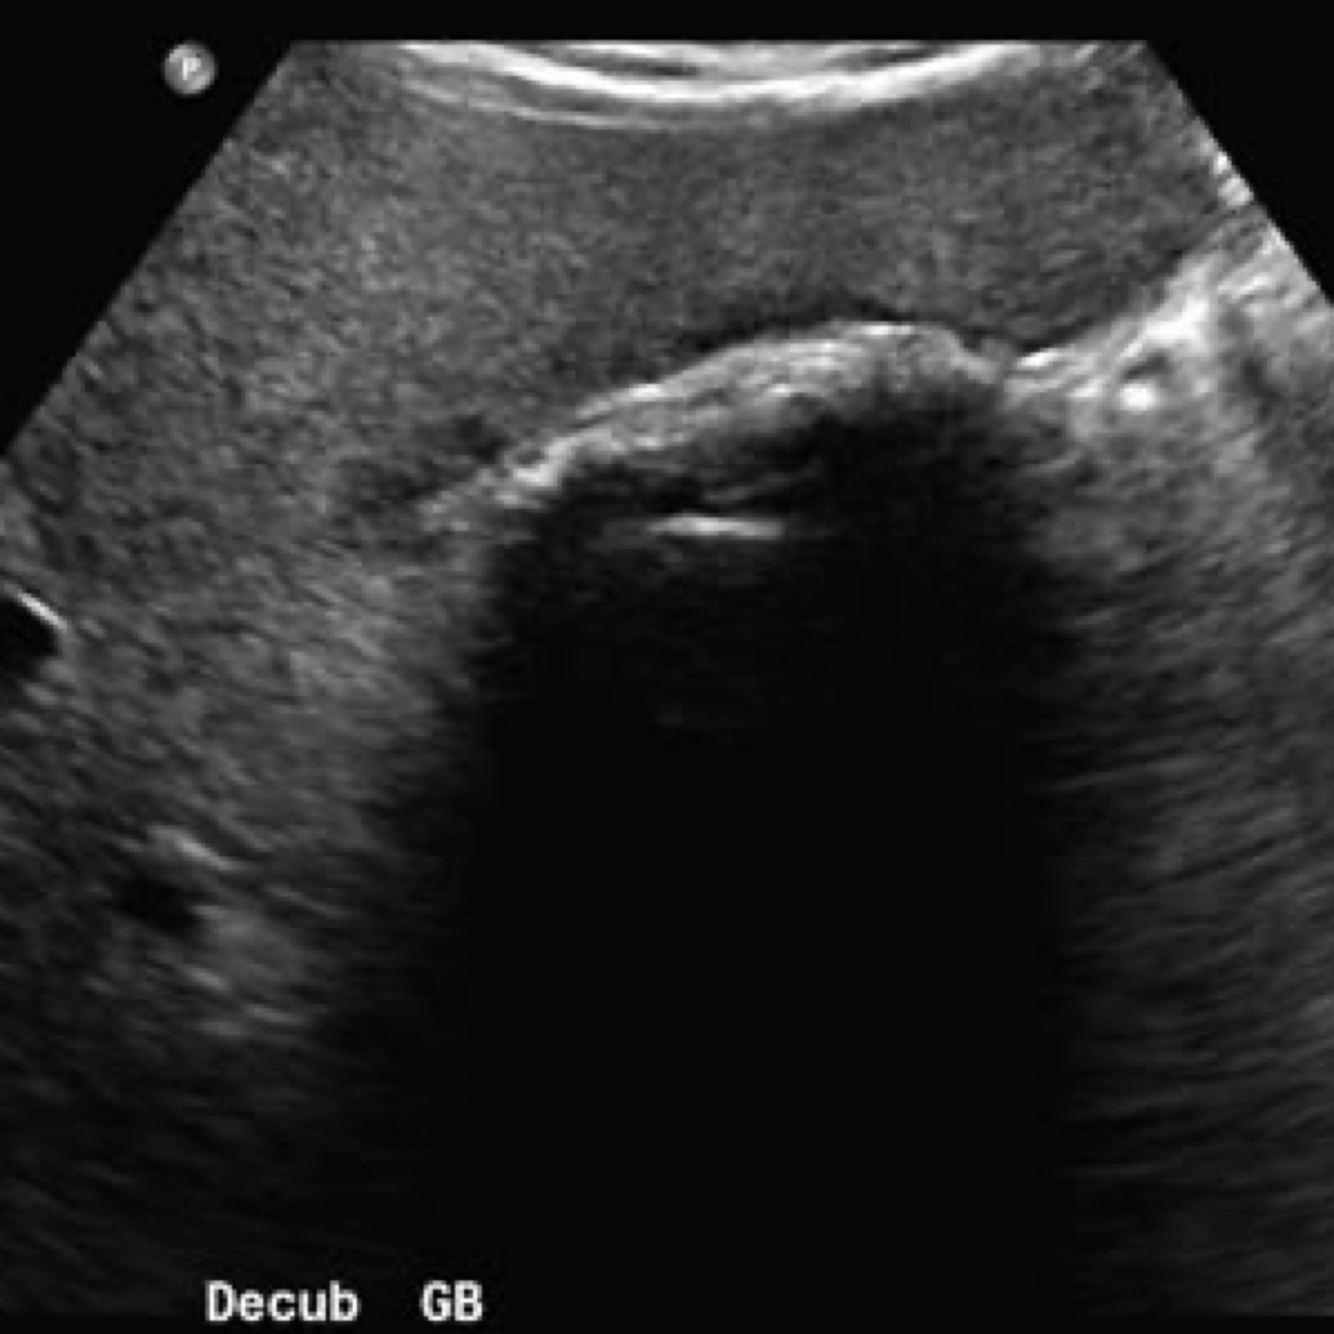

A

GB sludge

May be caused by conditions

●Prolonged fasting

●Total parenteral nutrition (TPN)

●Bile stasis

●Pregnancy

●Rapid weight loss

●Recent surgery

Biliary sludge